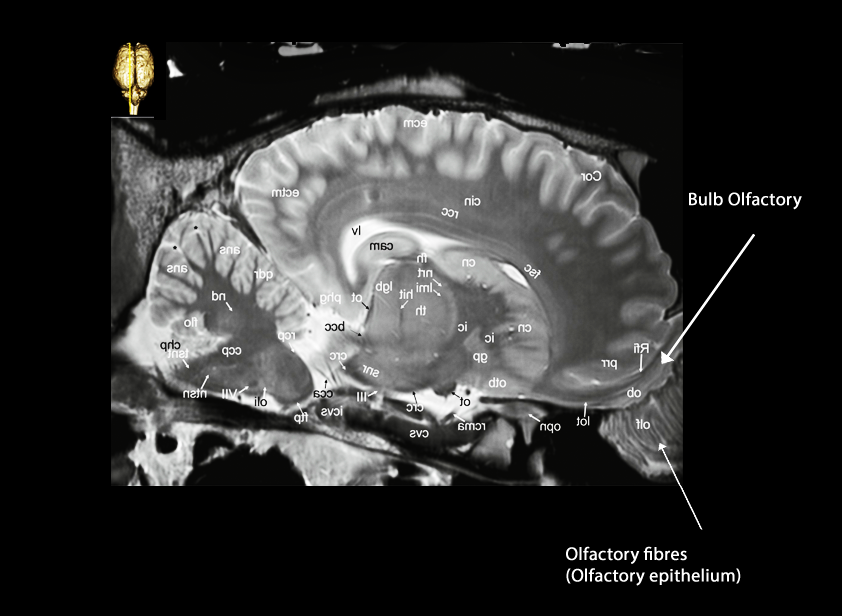

Olfatory system.

The horses have two mechanisms to detect odor;

1. One is by means of the main olfactory system (MOS), with the main olfactory receptors (MOrs) located in the posterior part of the mucosa of the nasal cavity. The olfactory nerves project to the main olfactory bulb (MOB), from where the olfactory tracts transmit their inputs to specific areas of the brain: the anterior olfactory nucleus, piriform cortex, olfactory tubercle, anterior cortical amygdaloid nucleus, the lateral entorhinal cortex and the periamygdaloid cortex.

2. The other option is through the accessory olfactory system (AOS), commonly named the vomeronasal system (VNS). It is integrated by three different structures: the vomeronasal organ (VNO), the accessory olfactory bulb AOB, and the vomeronasal amygdala (VNAg). Inside the VNO are the vomeronasal receptors (VNrs), which project through the vomeronasal nerves to the AOB. The horse uses its VNO during the flehmen response, activation of pheromone uptake, in which it raises its head and rolls back its upper lip , forcing smell-laden air through slits in the nasal cavity into the VNO . The pheromone is a secreted or excreted chemical factor that tiggers a social response in member of the same species. The response is often seen in horses conducting a thorough investigation of other horses' urine and feces but may also occur when they encounter novel flavors and nasal irritants. Although gravity assists in this sampling procedure, it has been shown that the lumen of the tubular portion of the VNO alternatively expands and contracts to pump its content in the direction of the accessory olfactory bulb. In contrast to many other species, the VNO of horses does not open into the oral cavity.